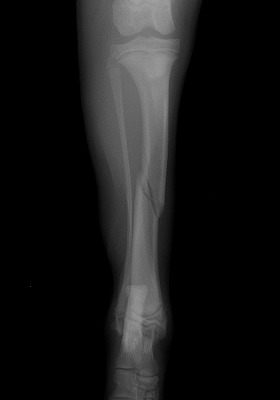

家の中で遊んでいると「キャイーン」という悲鳴と共に片方の足を地面に付く事が出来なくなり来院されました。レントゲンを撮り調べてみると骨折していることが判明。

Img5978-1.jpg